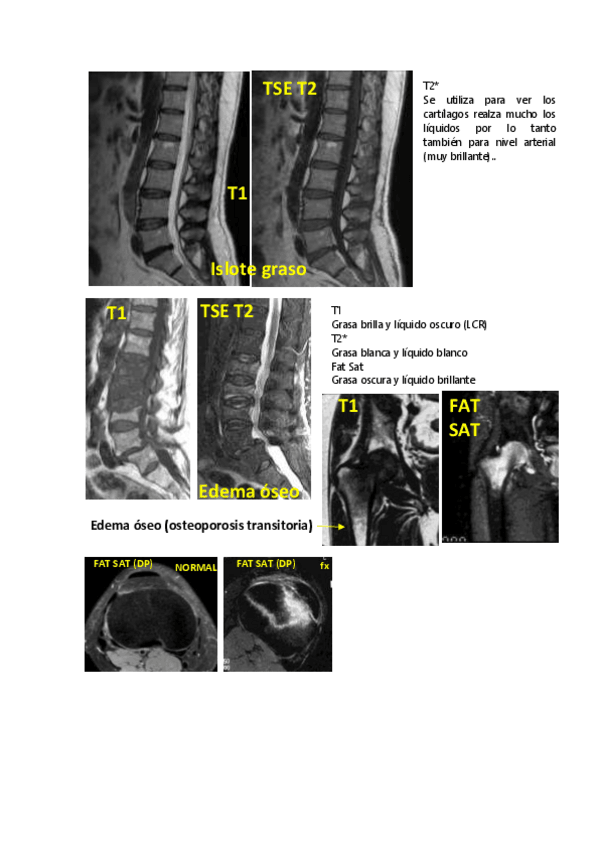

He publicado nuevos apuntes de 4º IMAGEN CLÍNICA EN FISIOTERAPIA: TEMA 5.pdf

5 páginas